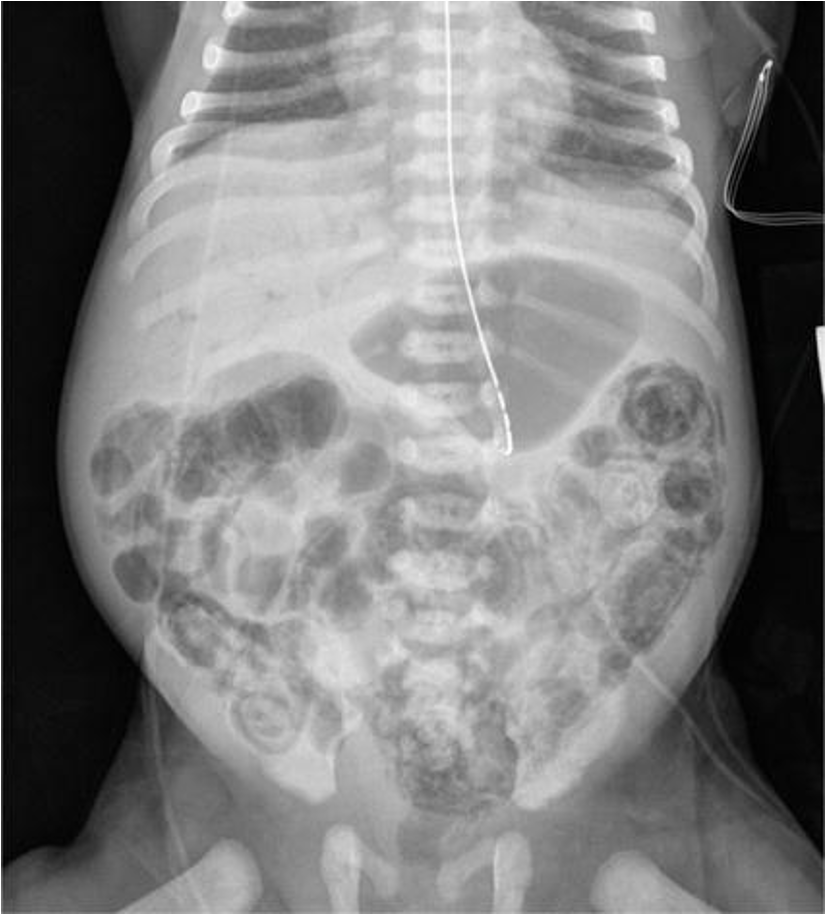

Preterm 29-weeks gestation C/S delivery showed severe respiratory distress soon after birth. This chest x-

ray was taken at age of 6 hours.

Q1: ground glass appearance, wide intercostal space.

Q2: Neonatal respiratory distress syndrome.

Q3: mechanical ventilation, give Surfactant for lungs maturation.

Xray findings

- White lung

- Air bronchogram

- Ground glass appearance

- low lung volume

What is your diagnosis? RDS

What is the definite treatment? Surfactant.